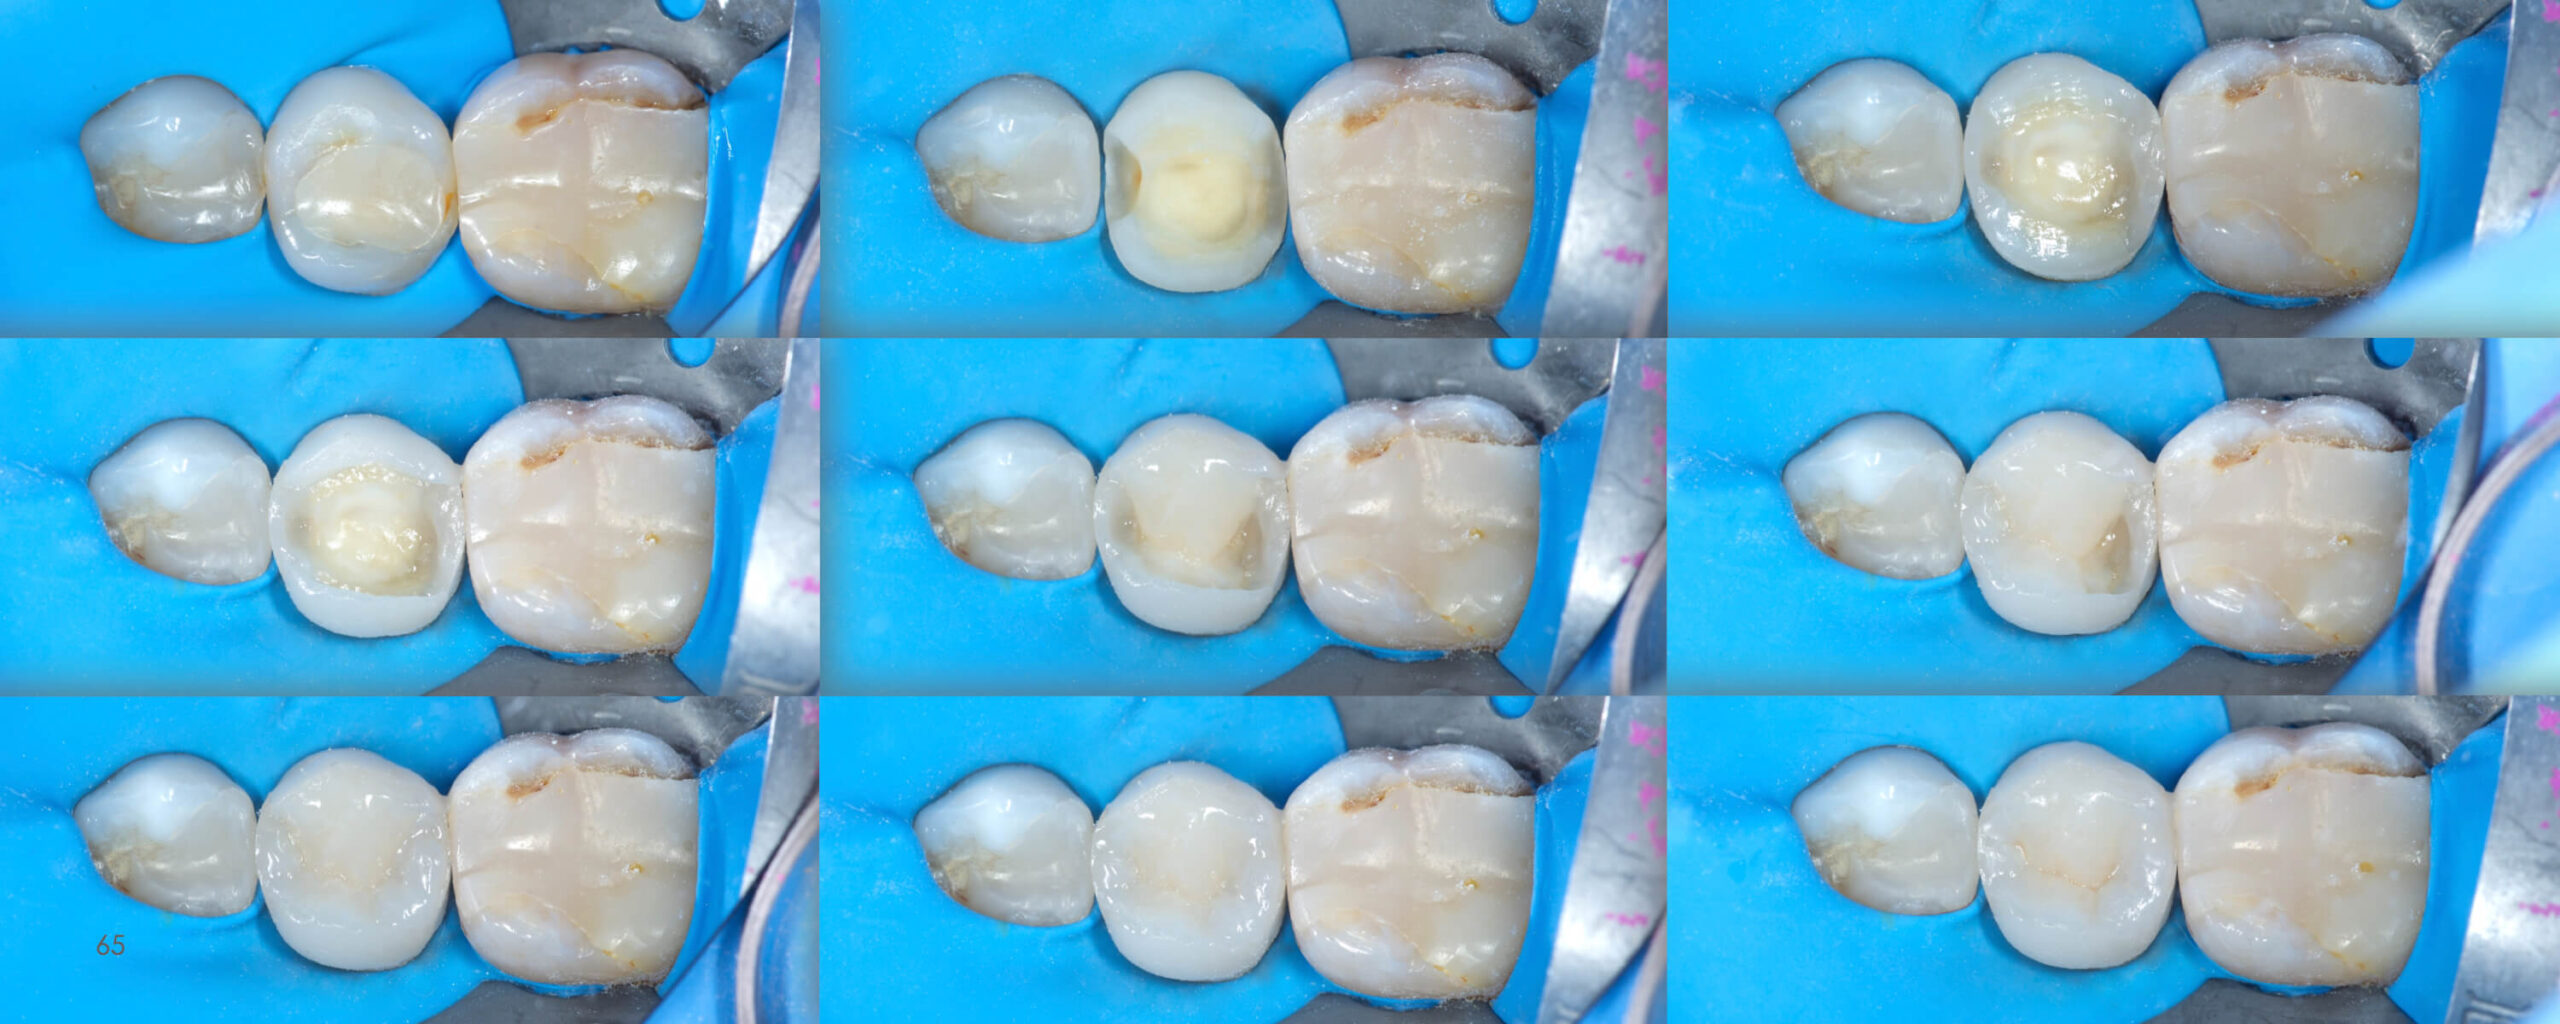

Posterior Teeth Morphology

Direct Composite Restorations

The atlas is a compendium of knowledge about the anatomy of posterior teeth. It is addressed to dentists who want to increase their

practical skills in direct restorative work.

You’ll find the answers to this and more. After reading this atlas, you will be prepared how to create the biomimetic

restoration using direct method.